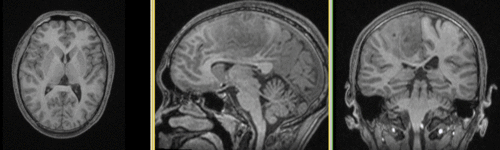

Slicer Registration Library Case #27: Intra-subject Brain DTI

This is a classic case of a multi-sequence MRI exam we wish to spatially align to the anatomical reference scan (T1-SPGR). The scan of interest is the DTI image to be aligned for surgical planning/reference.

MRI, brain, head, intra-subject, DTI, T1, T2, non-rigid, tumor, surgical planning